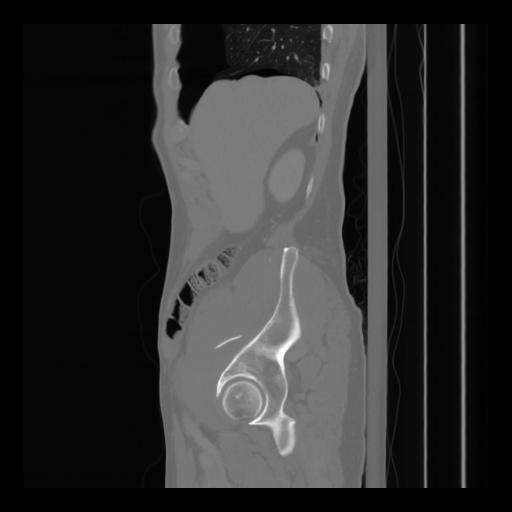

36 CUERPO,CE,Sagittal,3.000,CUERPO,Sagittal,